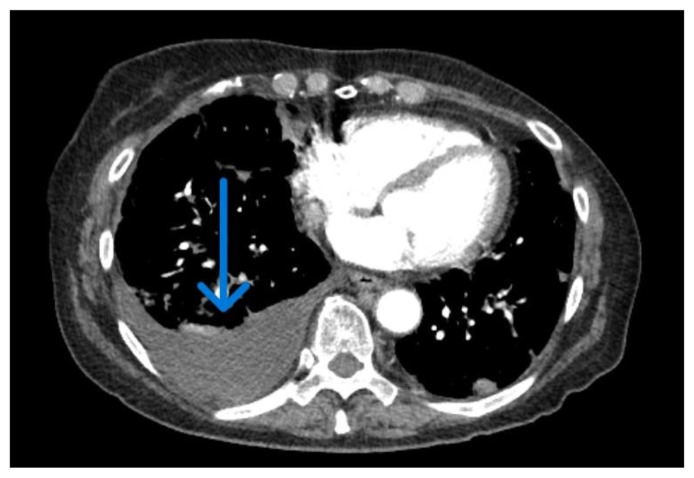

In the landscape of pancreatic cancer, extra-pancreatic manifestations like pleural effusion are infrequent. Our case spotlights a 78-year-old female with a recent diagnosis of pancreatic adenocarcinoma with isolated metastasis to the pleura. The patient presented with exacerbated dyspnea and cough, shedding light on the uncommon link between pancreatic adenocarcinoma and pleural effusion. Pancreatic cancer typically exhibits nonspecific symptoms, and its association with pleural effusion significantly complicates diagnosis, often leading to delayed recognition and management challenges. This case underscores the diagnostic complexities and the need for heightened vigilance when faced with atypical presentations in pancreatic cancer, emphasizing the intricacies of managing such rare extra-pancreatic manifestations.